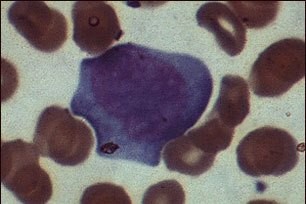

Бұл - "жалған жасуша", инфекциялық мононуклеозда кездеседі, ВЭБ (Эпштейн-Барр вирусымен) немесе ЦМВ (цитомегаловируспен) жұқпаланатын лимфоцит. Мононуклеозда лимфоциттердің үш түрін бөлуге болады. Бұл лимфоцит II типті жасушаға жатады.